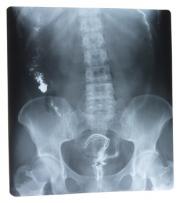

Jednak przed podjęciem leczenia bezwzględnie należy wykonać zdjęcie rentgenowskie bolącego odcinka kręgosłupa, gdyż objawy podobne do dolegliwości zwyrodnieniowych mogą być skutkiem innym chorobom kręgosłupa.